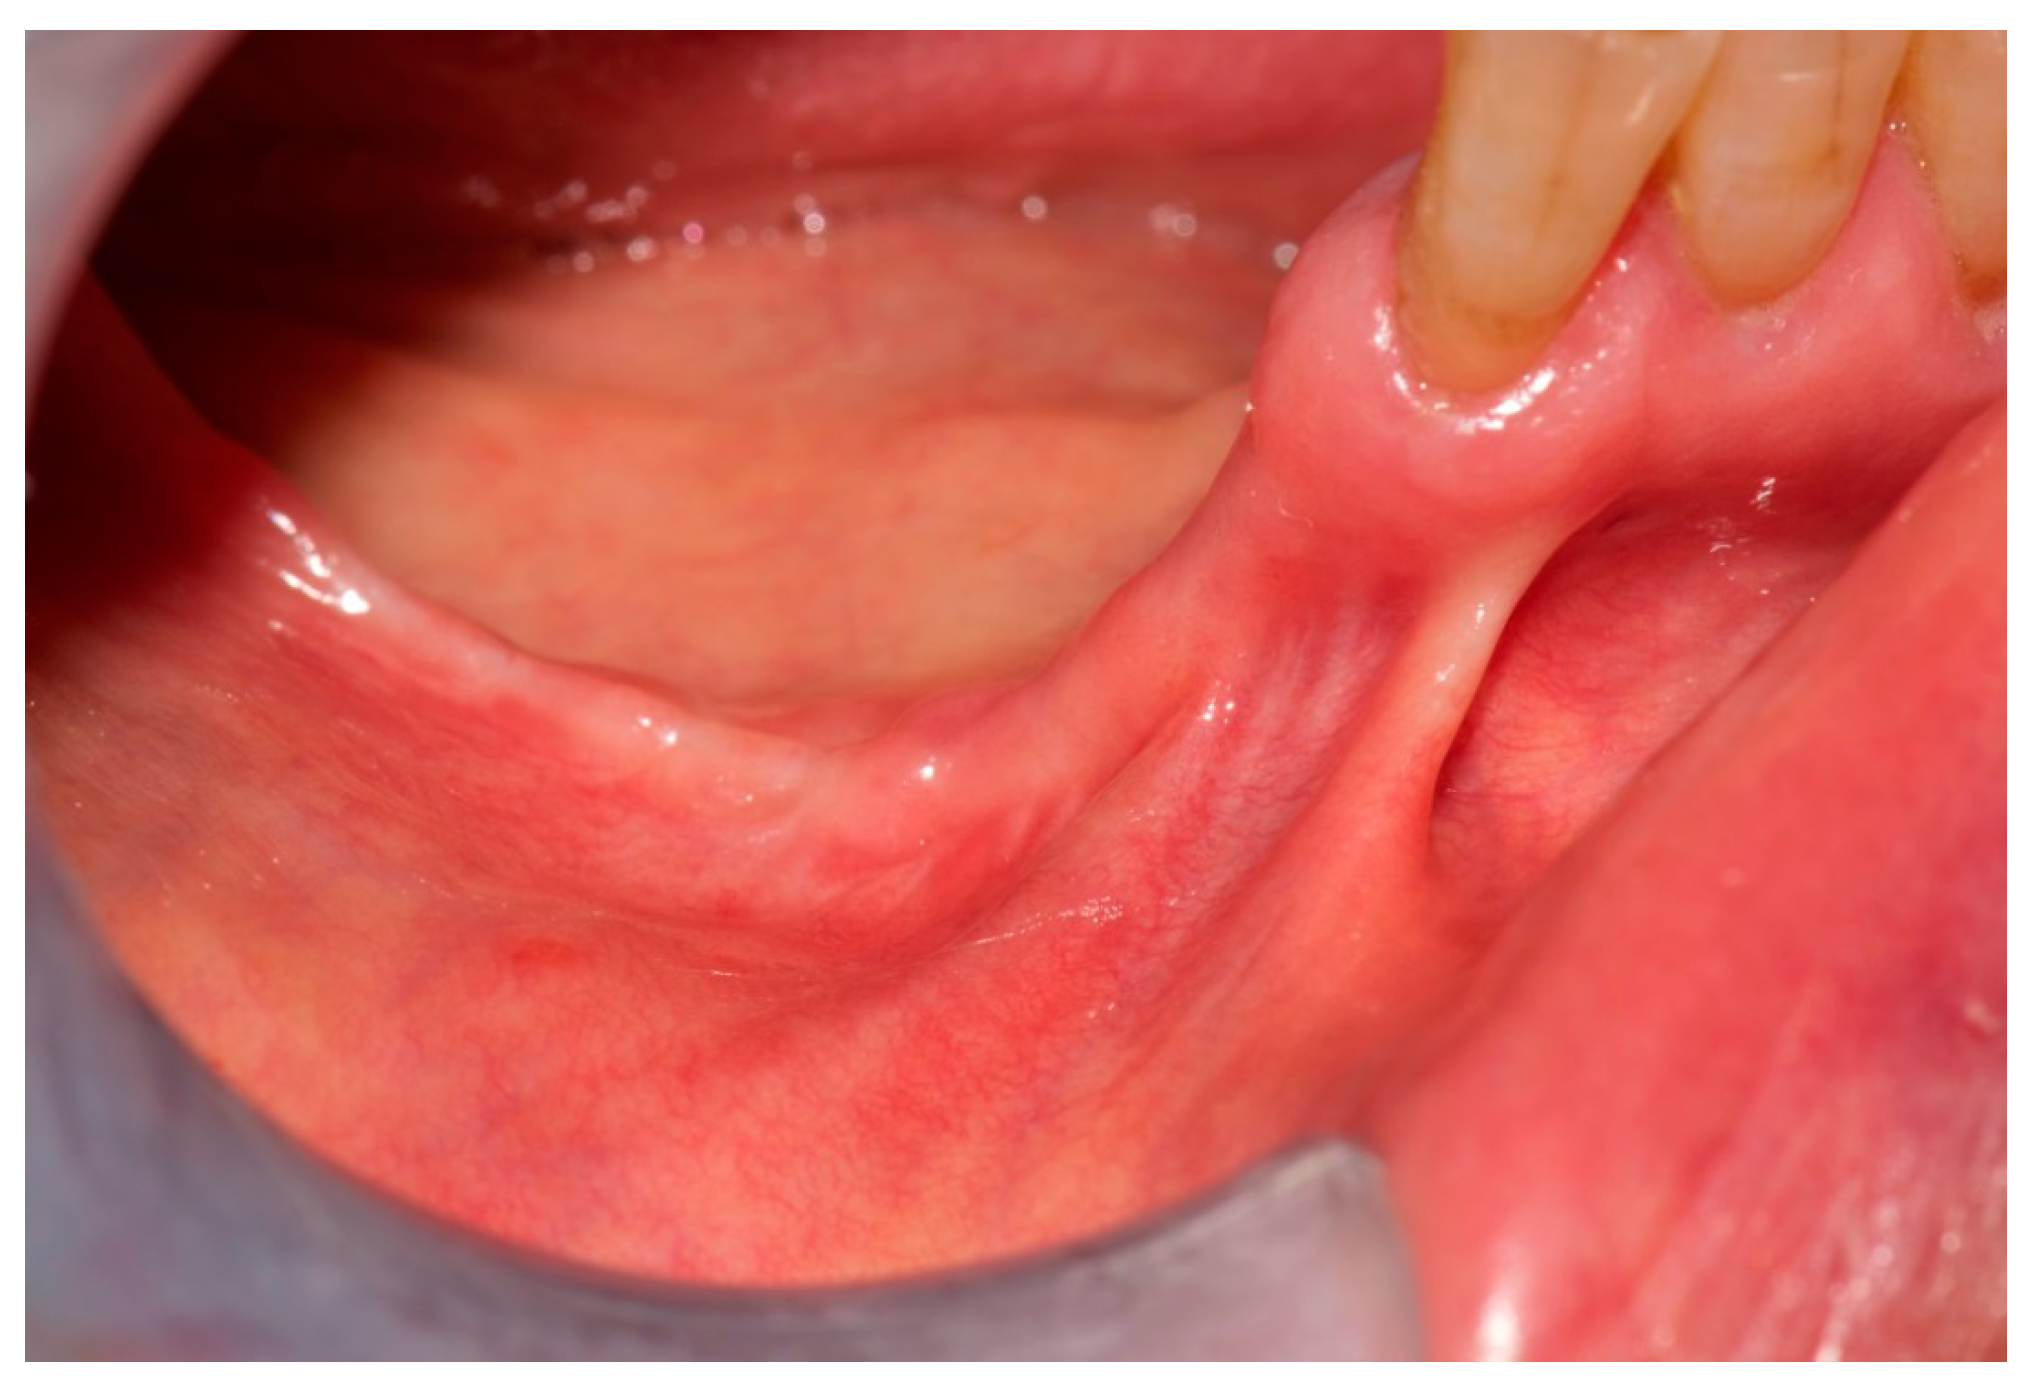

2. Case Report